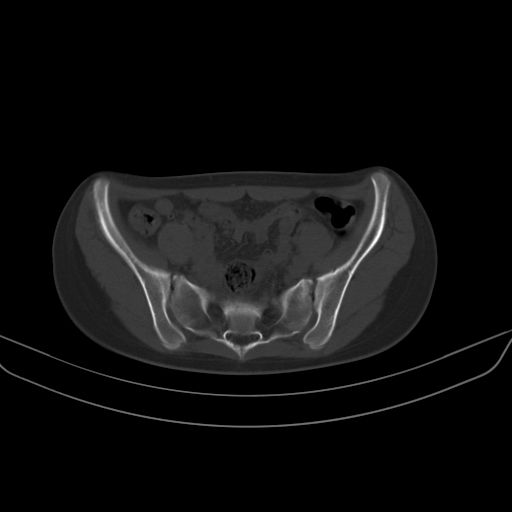

以下是引用zsl6918在2008-7-11 21:40:00的发言:[br]双侧骶髂关节骨质破坏以下三分之一为主,符合强直性脊柱炎表现

以下是引用zhangzhongshou在2008-7-11 21:41:00的发言:[br]患者是女性,hla-b27抗原(—),首先不太考虑强直性脊柱炎,建议查类风湿因子,骶髂关节改变考虑类风湿性关节炎可能性大,建议进一步检查。